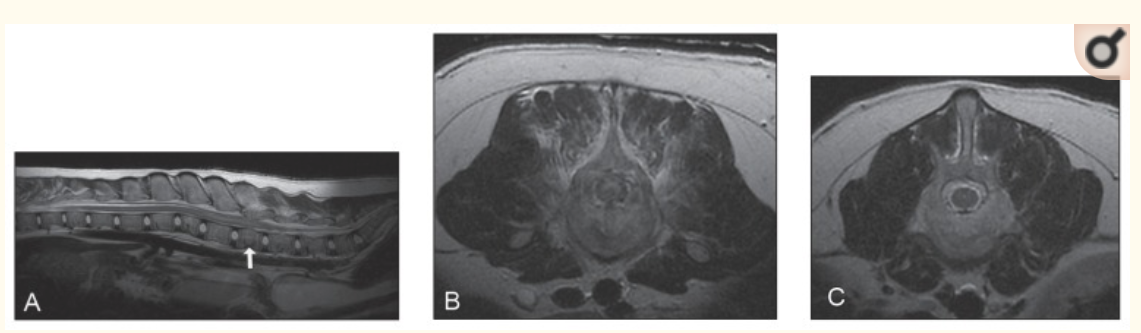

因飲食營養不均衡導致壓迫性骨折、維生素D缺乏及營養性繼發性甲狀旁腺功能亢進